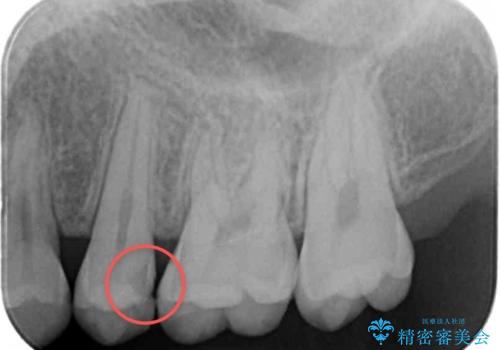

- 外から見える範囲の銀歯のやり替えをご希望で来院されました。

セラミックインレーでの治療となります。

- 左上45 セラミックインレー 77,000円×2本 費用は治療当時の料金となります

奥歯とはいえ今回のようなケースでは笑った時に銀歯がちらつきます。

白く目立たないセラミックインレーが入ったことで大変喜んでいただけました。